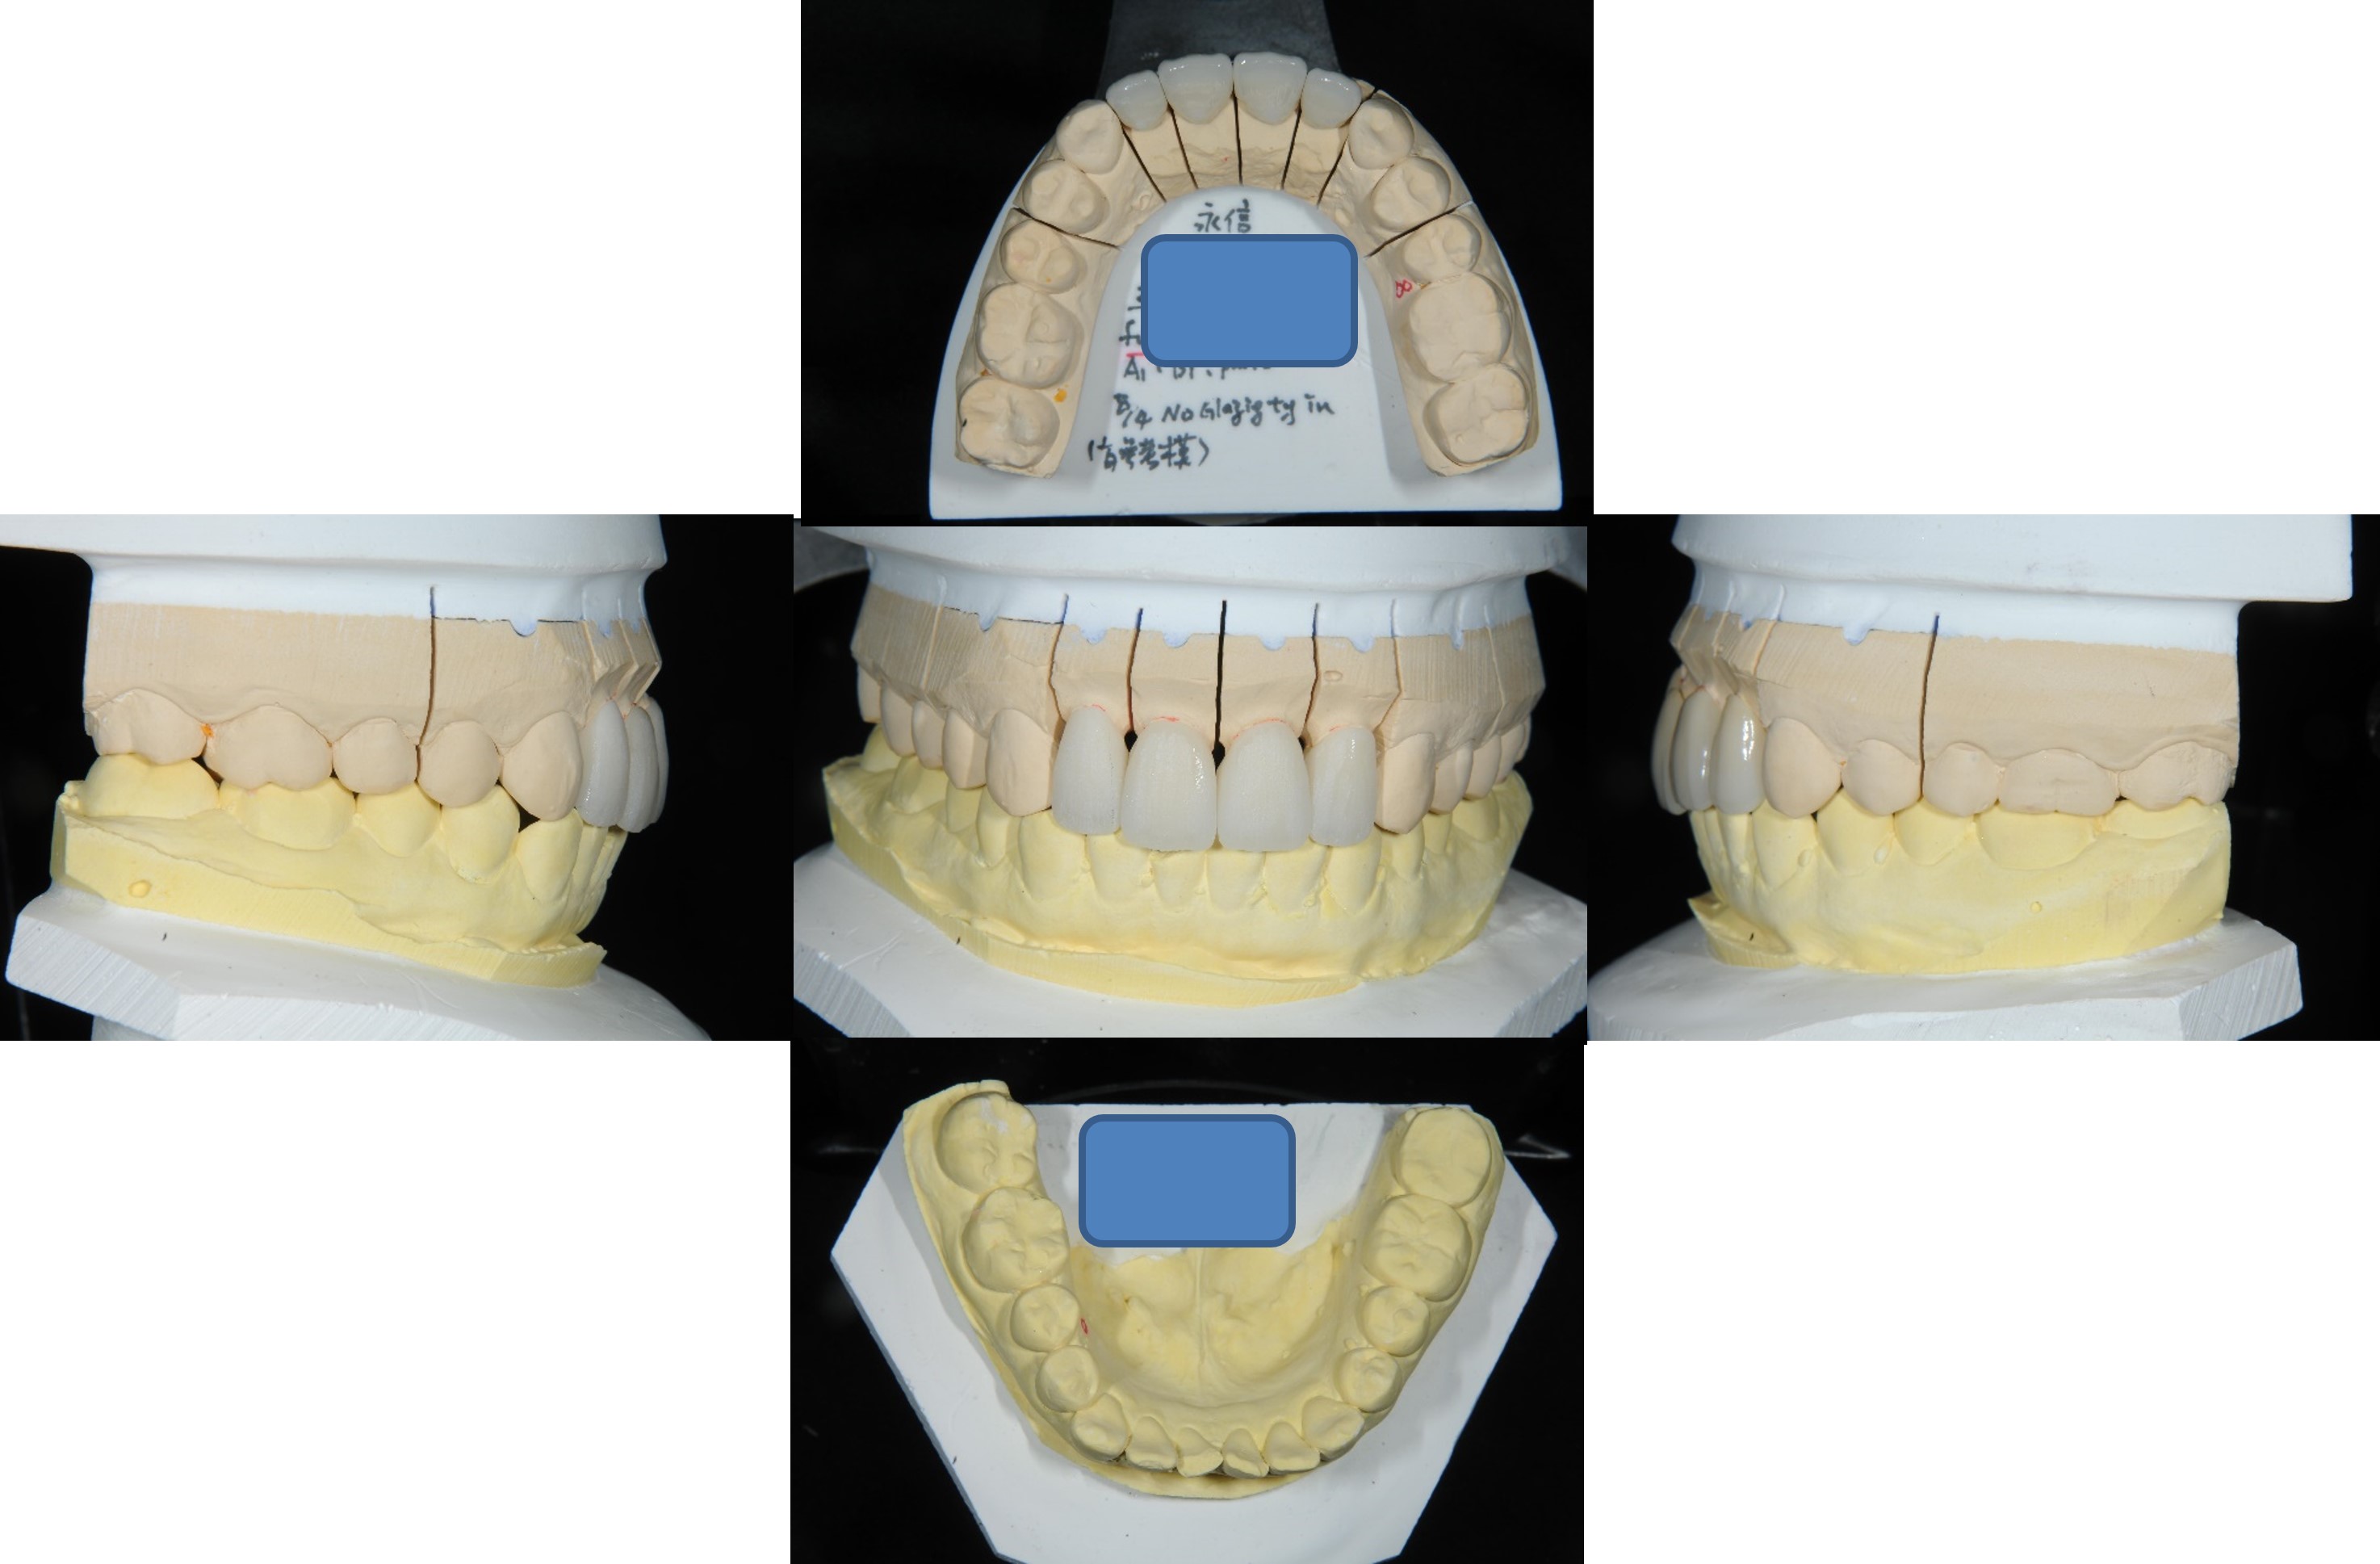

咬合器上製作全瓷冠

口內調整瓷牙邊緣